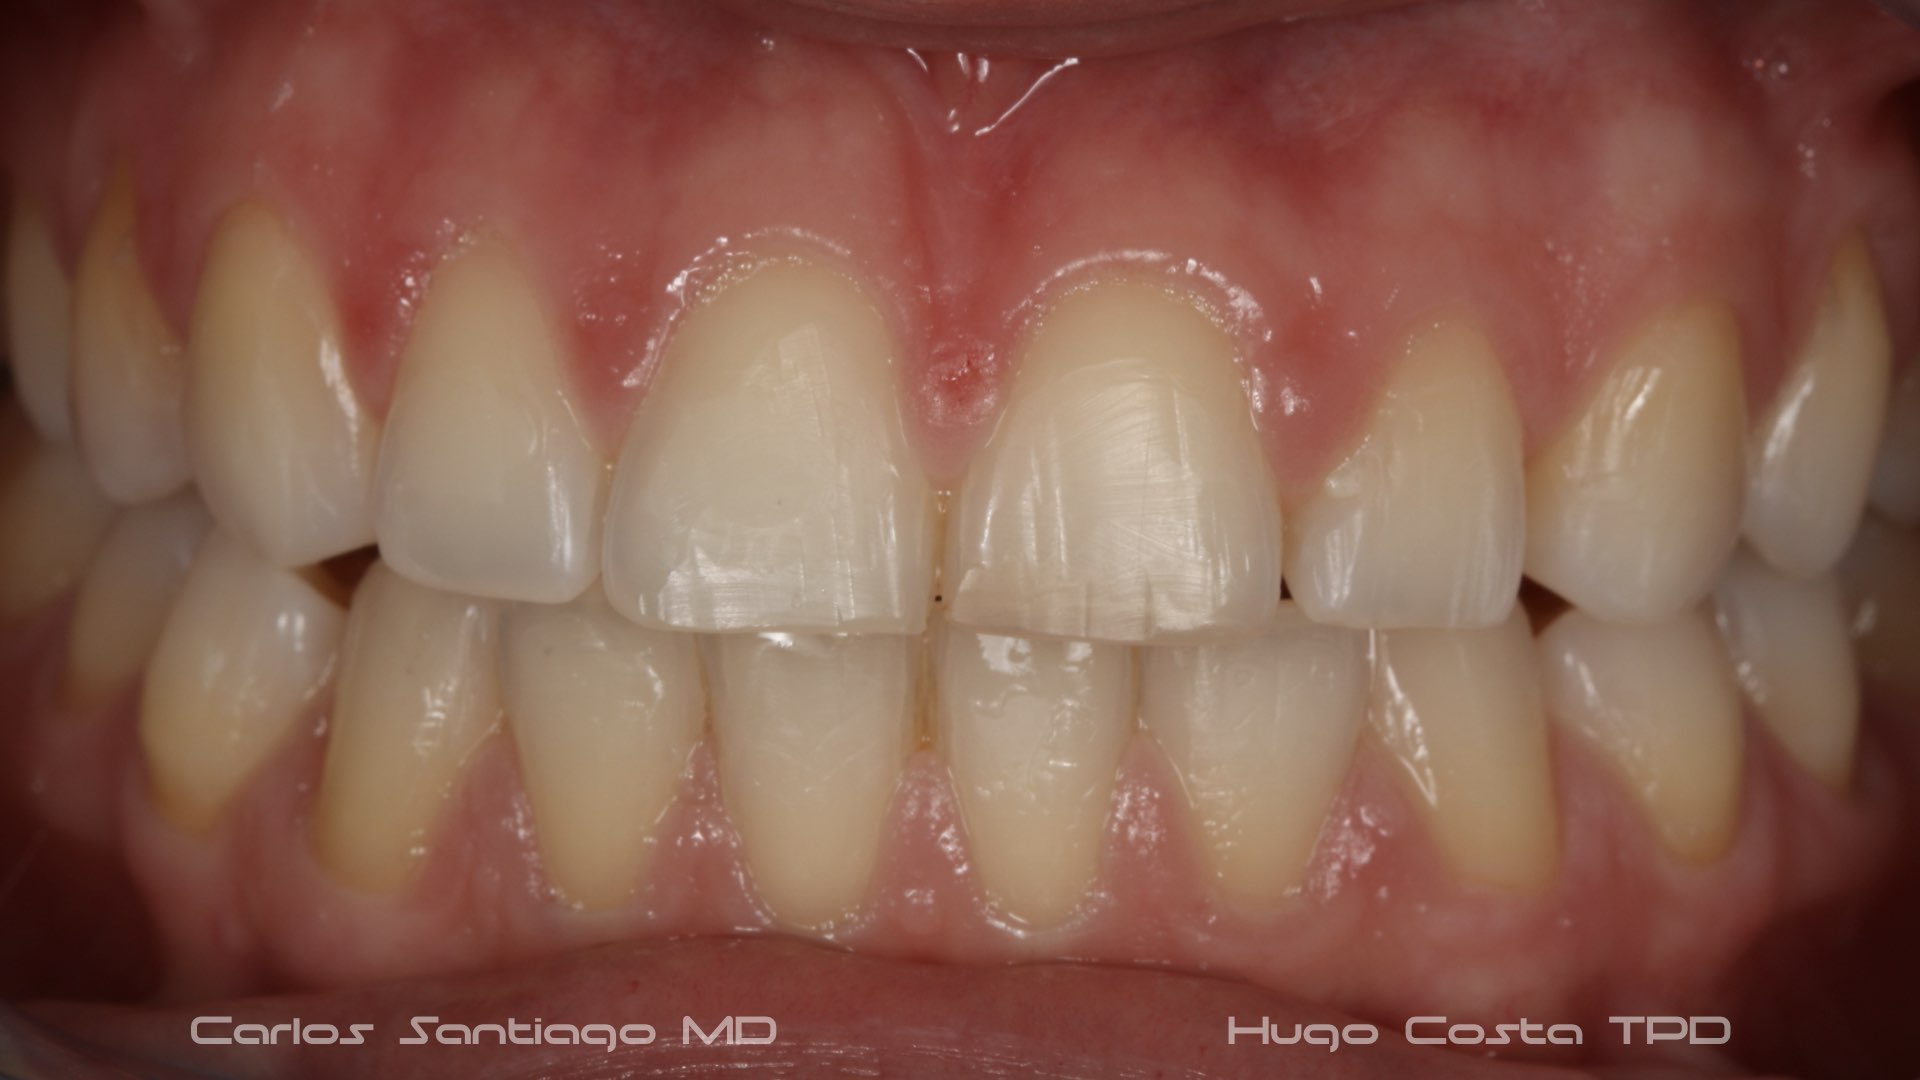

As Facetas Cerâmicas (lentes de contacto dentárias ou laminados), permitem corrigir da maneira mais estética e conservadora possível, problemas de forma e tamanho, côr e posição dos dentes, bem como substituir restaurações antigas e inestéticas.

São aderidas químicamente ao esmalte dentário de uma forma permanente, com o objectivo de melhorar a estética dos nossos pacientes.